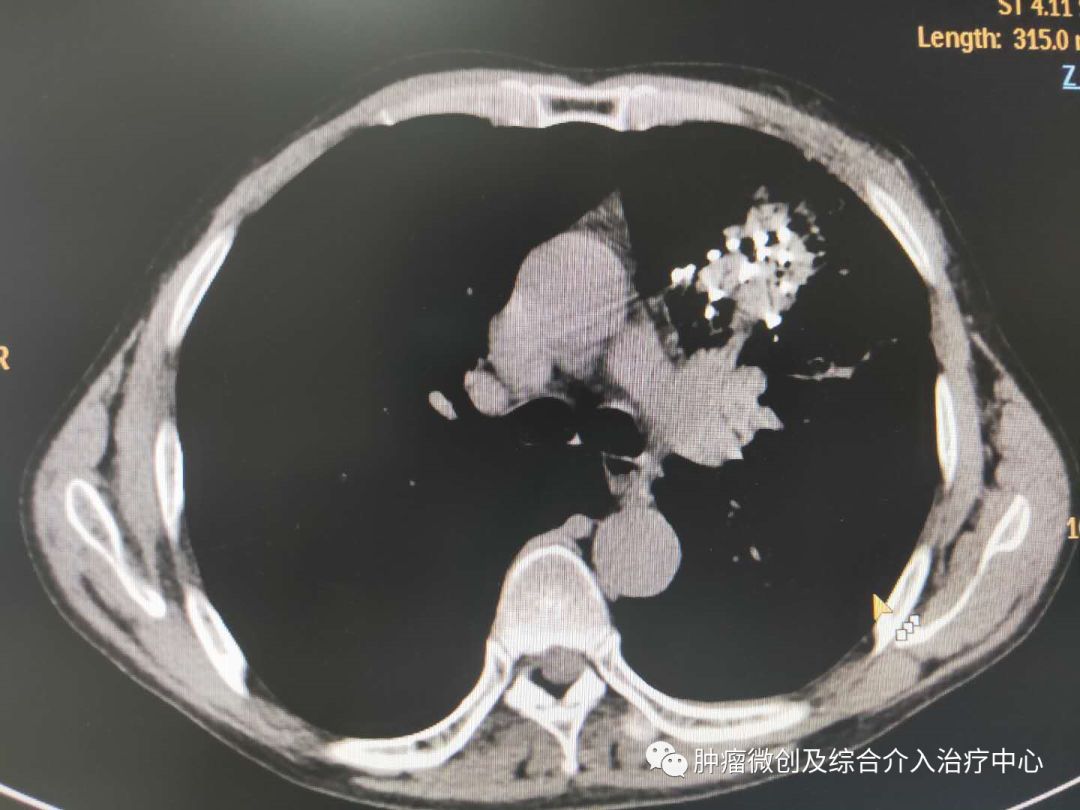

患者老年男性,70岁,患者,北京肿瘤医院确诊为左肺恶性肿瘤,低分化,骨转移,行放疗,化疗无效,影响睡眠及日常活动,为求进一步治疗就诊运城市第一医院肿瘤微创及综合介入科专家门诊,诊断为“左肺恶性肿瘤”收入院。入院后完善术前检查,经李辉教授及全科医生讨论后决定行碘125放射粒子植入术,通过内放射杀灭肿瘤细胞,缩小肿块,缓解症状。2019-04-29于CT室在局麻下行放射粒子植入术,术中通过CT精确定位后穿刺放置放射粒子共计40颗,均匀分布在肿块内部。手术过程顺利,患者无明显不适主诉,术后安返病房。术后3天患者症状明显减轻。

1.术前CT显示肿物